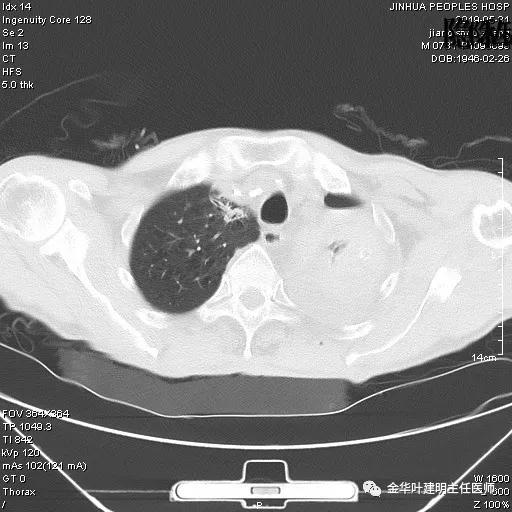

患者,男性,73岁,金华人。因“咳嗽咳痰伴胸闷2月,检查确诊左肺癌1周”入院。气管镜: 气管支气管内较多脓性分泌物,左肺上叶前段管腔新生物,局部活检、毛刷。气管镜病理:(左肺活检)鳞癌。阅胸部CT见左上叶开口处新生物,考虑需左上叶袖式切除及淋巴结清扫。具体CT表现如下:

考虑左侧大量胸腔积液,遂进一步胸部CT检查:

以上是肺窗表现,下面为纵隔窗影像: